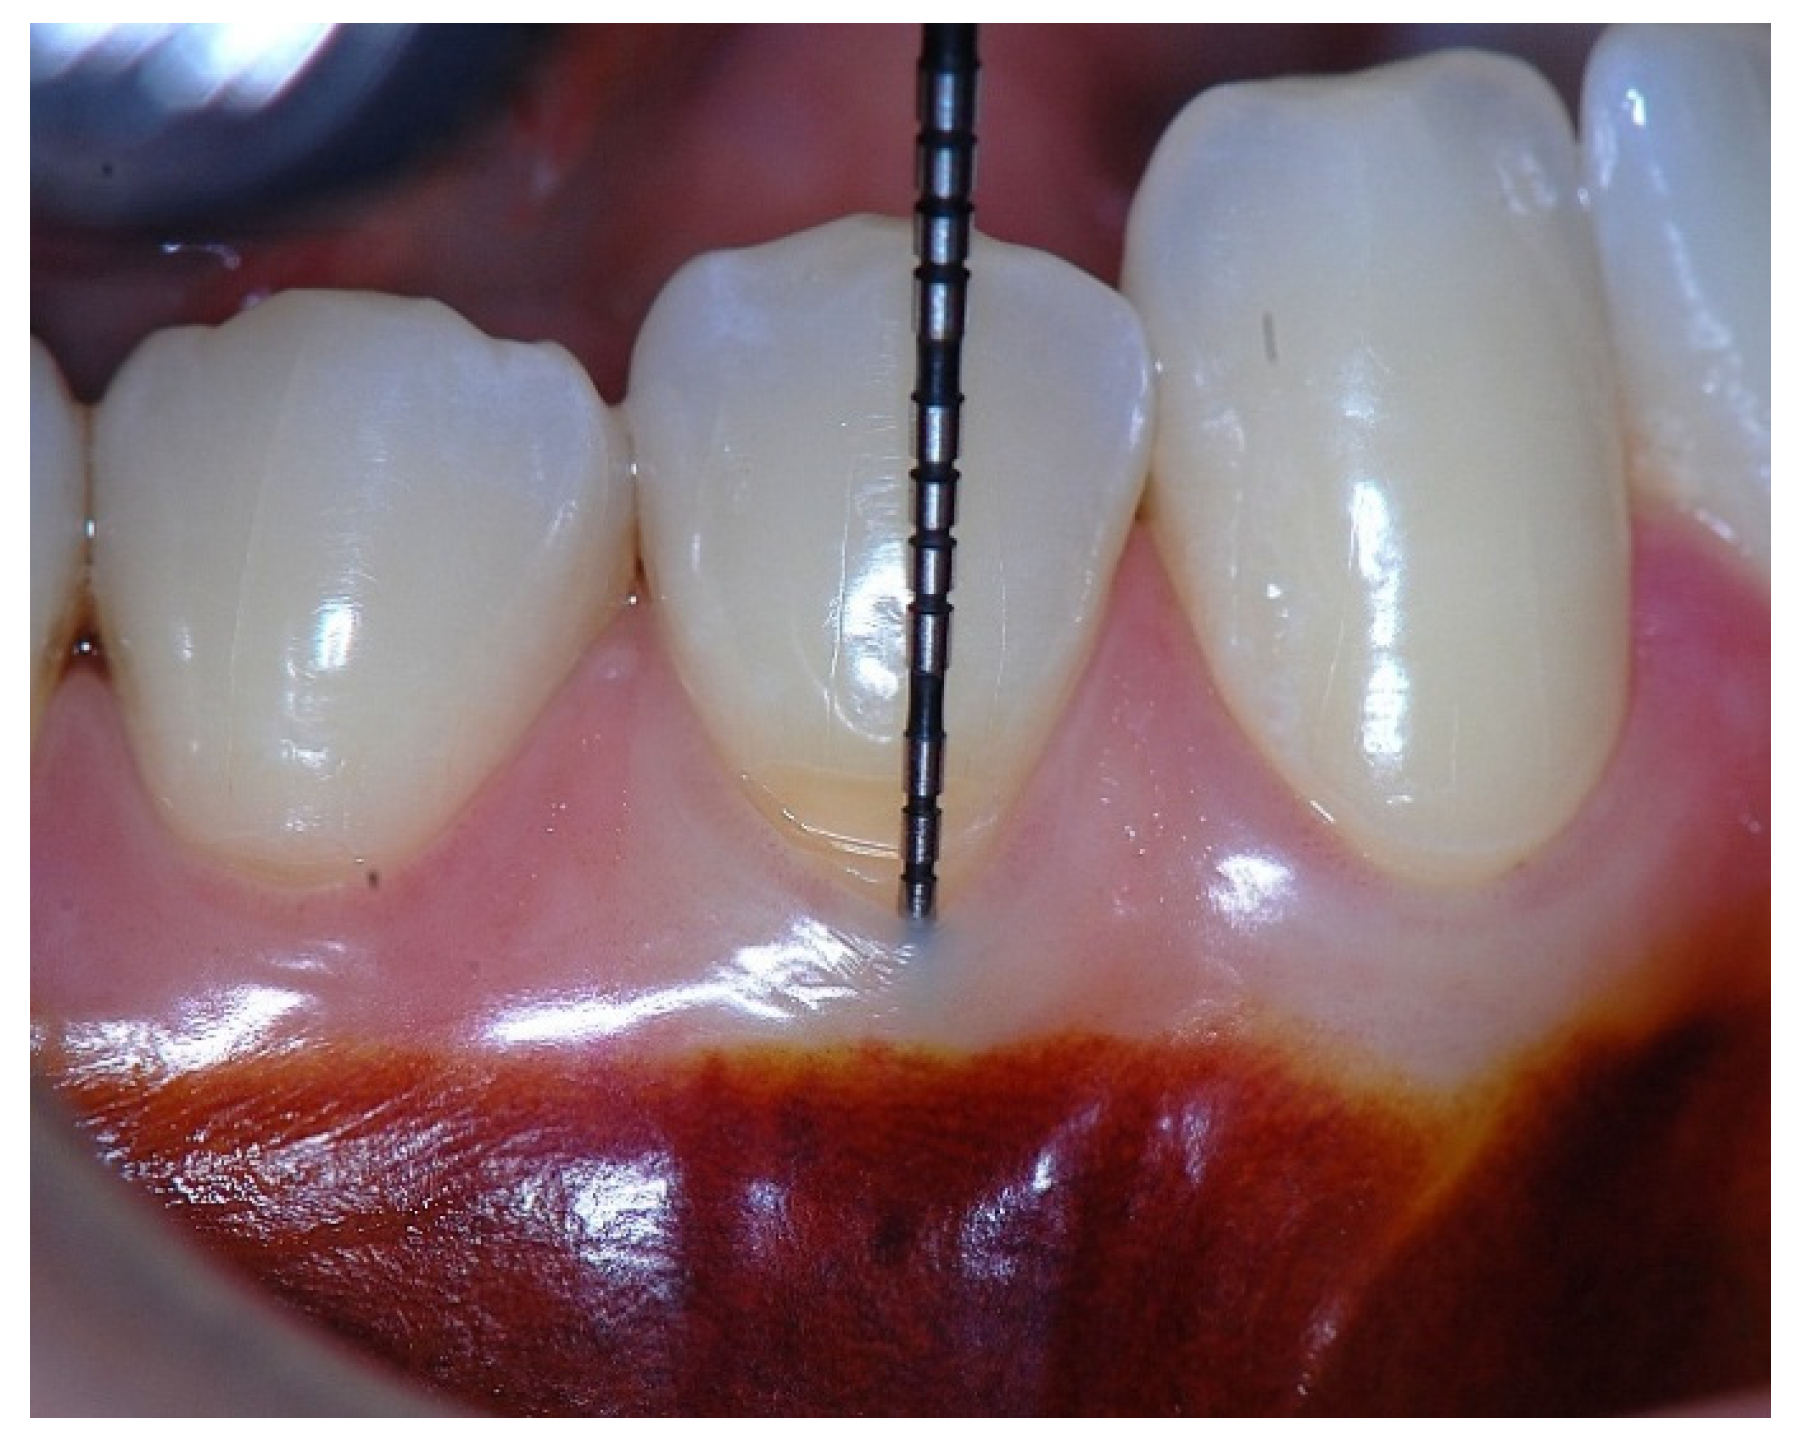

Figure 4. Probing depth of 1 mm associated with 1 mm of epithelial attachment and 1 mm of connective tissue fiber insertion into the root cementum.

In a clinical scenario characterized by 2 mm of keratinized tissue and a sulcus depth of 1 mm, a stable and mechanically resistant connective tissue attachment is not present [1]. This is attributable to the fact that most connective tissue fibers inserting into the root surface are associated with non-keratinized, mobile mucosal tissues (Figure 1), which are elastic in nature and therefore incapable of stabilizing the gingival margin (Figure 2 and Figure 3). In contrast, when these fibers are embedded within keratinized tissue, they are firmly anchored to both the tooth and alveolar bone and are comparatively immobile, thereby contributing to gingival margin stability (Figure 4, Figure 5 and Figure 6).

To achieve predictable resistance to mechanical trauma, a keratinized tissue width of approximately 3 mm appears necessary, assuming a sulcus depth of 1 mm, thereby allowing for 1 mm of epithelial attachment and 1 mm of dense connective tissue attachment to the root surface [21,33].